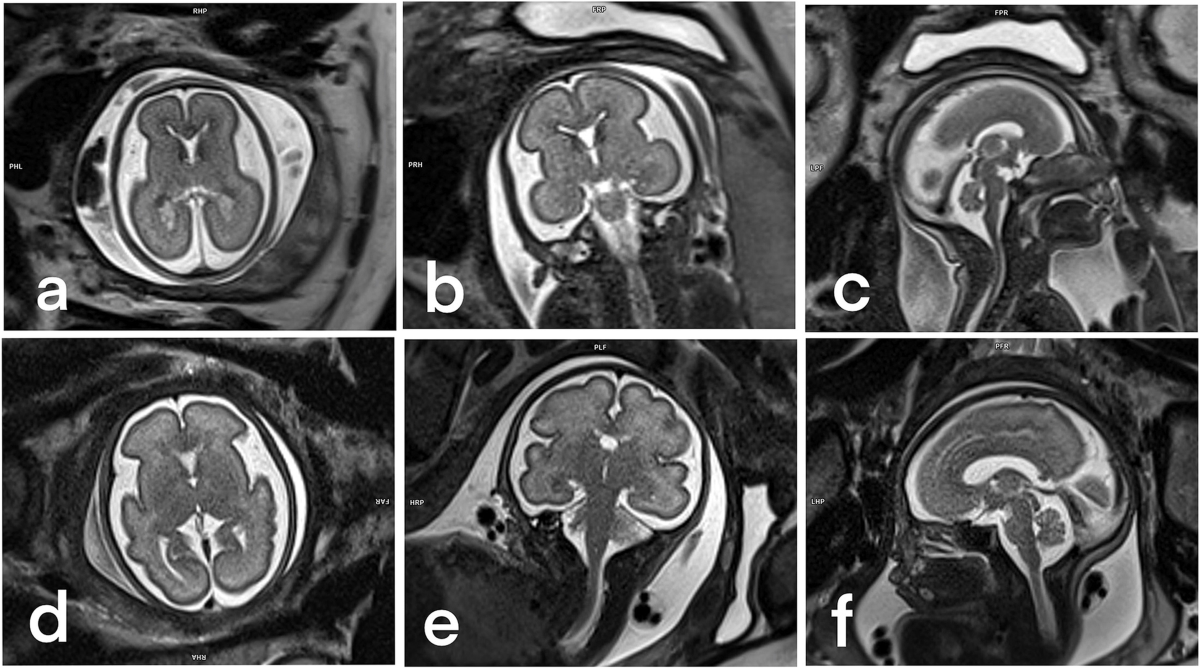

Fetal MRI images have recently captured global attention thanks to their breathtaking — and slightly mysterious — appearance. These scans, verified by medical experts and supported by research from institutions like Harvard Medical School, The National Institutes of Health (NIH), và Radiological Society of North America (RSNA), offer one of the most detailed views ever of human development before birth.

At first glance, the bright, prominent eyes and unusual facial expressions seen in fetal MRI scans may look a bit “alien.” This appearance is perfectly normal and happens because MRI technology captures body tissues very differently from ultrasound. While traditional ultrasound uses sound waves to create smooth, familiar outlines, MRI uses strong magnetic fields and radio waves to produce high-contrast images of the brain, organs, muscles, and blood vessels. As a result, certain features — especially the eyes and facial structures — appear more dramatic and intense.

Although adult MRI scans can also look otherworldly, fetal MRIs reveal something truly unique: the extraordinary complexity of life before birth. Every image showcases the rapid formation of the brain, nerves, and senses — a beautiful illustration of how advanced medical imaging has become.